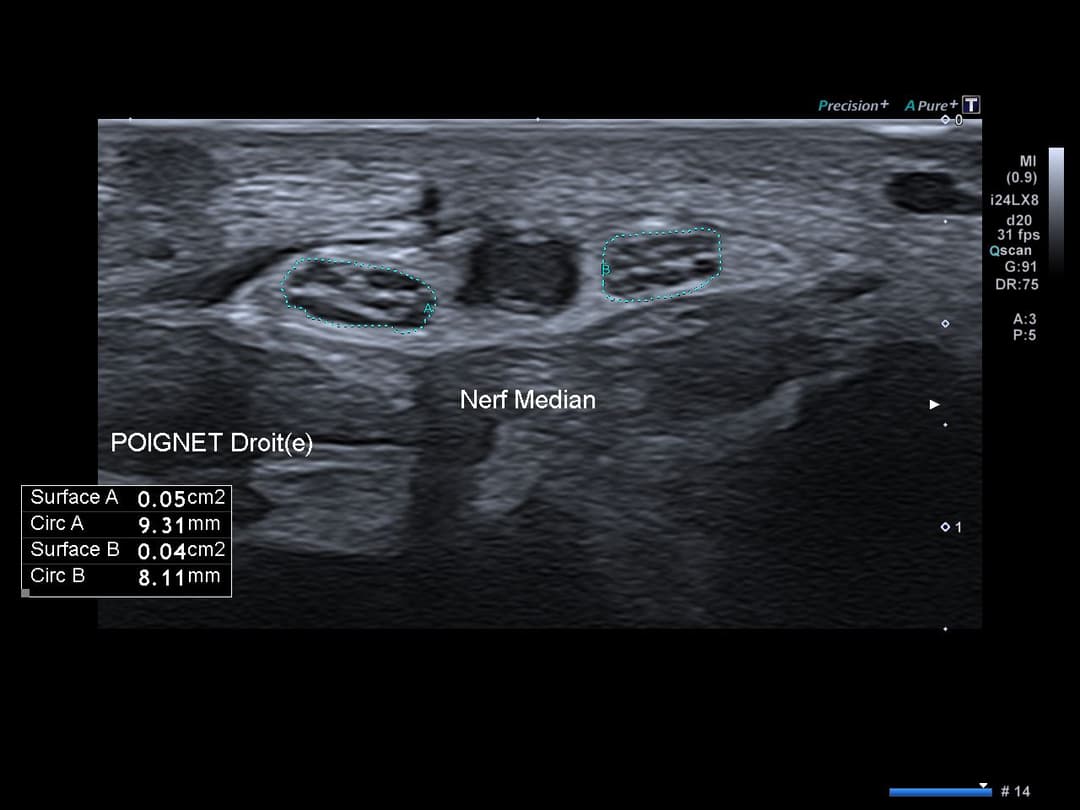

Nerf médian bifide de calibre additionnel dans les normes sans renflement notable.